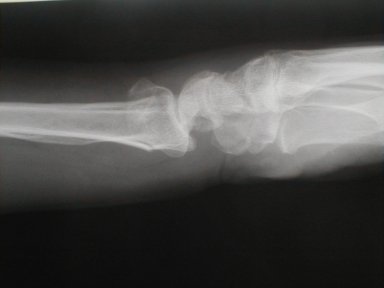

症例 9

左前腕骨骨折 コーレス骨折

72歳 女性

負傷原因   自宅近くを犬の散歩中足元が凍っていたために、すべり転倒した際手をつき負傷

皮下溢血、腫脹著明で運動制限有り

橈骨が背側に転位しているのが、若干気になるが高齢者でもあり整復操作は愛護的におこなった